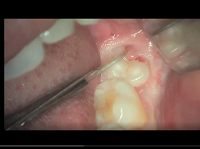

Oral Suergery (Zerodonto Dentistry) 2018

Spécialités : Stomatologie